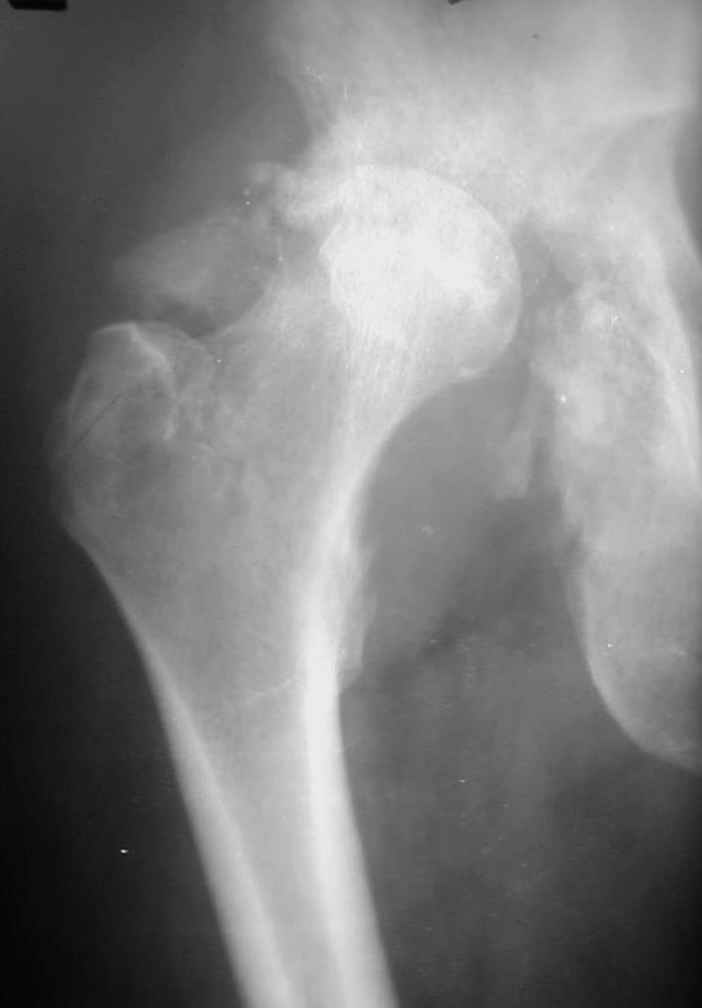

В институте совместно с фирмой Зиммер достаточно регулярно (практически ежемесячно) проводятся 2-х недельные циклы по различным вопросам эндопротезирования. Если есть возможность и желание, мы готовы поделиться с Вами нашим опытом, тем более есть что показать и что обсудить - в настоящее время ежедневно выполняется от 6 до 10 эндопротезирований коленного и тазобедренного сустава. В качестве примеров хочу показать 2 наблюдения, через 1 год и 5 лет после операции

1 год